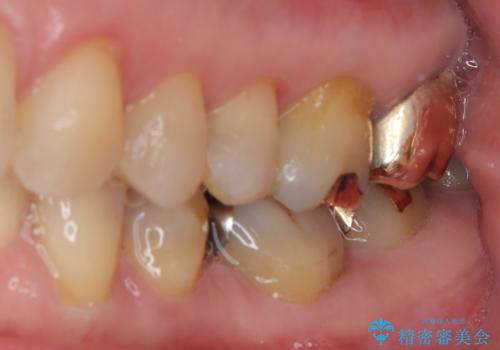

拡大鏡視野下で、保険のプラスチック、虫歯の除去を行い、セラミックインレーに適した形に整えました。

歯と歯茎の間に圧排糸と言われる糸を入れてシリコーン印象材にて精密な型どりをしました。